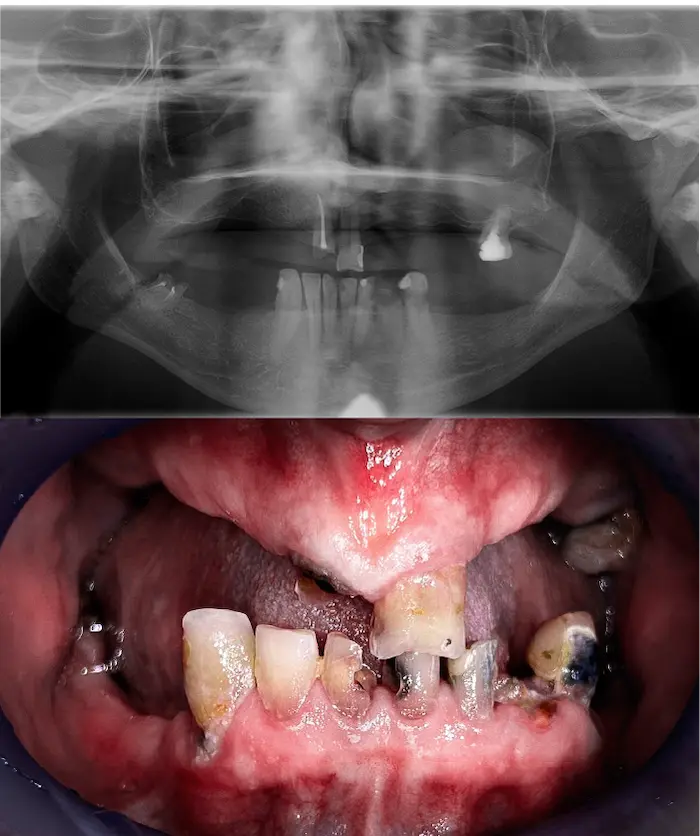

Molti pazienti arrivano con una storia simile:

Portano una dentiera mobile da molti anni

Non hanno abbastanza osso mascellare per gli impianti

Hanno perso i denti in giovane età e l'osso si è ritirato

Soffrono di atrofia muscolare importante

Sono soggetti a piorrea e mobilità dentale

Hanno già chiesto diversi pareri, senza successo

Queste condizioni rendono impossibili gli impianti fissi tradizionali o le riabilitazioni All-on.

E infatti molti professionisti li sconsigliano.

Una soluzione esiste: con gli impianti dentali zigomatici e gli impianti subperiostali (o impianti sottoperiostei) puoi ottenere denti fissi anche in assenza totale di osso mascellare.